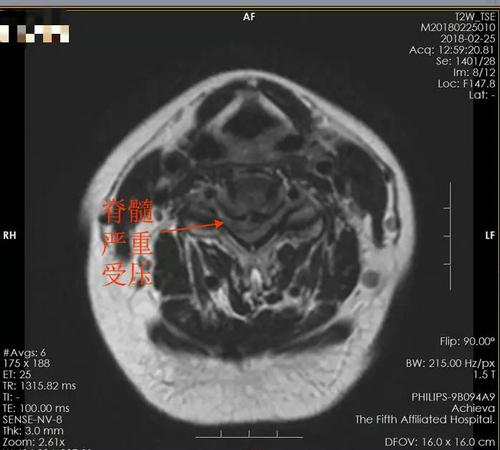

这一次,一直受到“脊髓型颈椎病”困惑的她因为对手术治疗的惧怕,偏信了某小诊所“按摩可以治疗一切颈椎病”的说法接受了按摩,结果出现“双下肢麻木,右上肢肌力减弱”的症状。小诊所的“大夫”告诉她这是正常现象,明天再来按一次就好了。第二天她又去按了一次,这次更糟了,竟然出现“双下肢瘫痪”,腕、肘、肩关节都不能正常屈伸,双手无力到连筷子也拿不起来了!这下私人诊所的“大夫”才惧怕起来了,告诉她这是得了“脑梗”,让她去神经内科治疗!

当天,赵女士被送到了郑州大学五附院神经内科,经过相关检查后排除了头颅问题,被诊断为“颈椎脊髓神经损伤”。

“本来临床上手术治疗效果很好的脊髓型颈椎病,结果因为不当的按摩造成了颈椎脊髓神经损伤,这种在原有颈椎病的基础上造成的颈脊髓神经损伤如果得不到及时治疗,就会给患者带来终身瘫痪甚至危及生命的危险!” 会诊后脊柱骨病科张长江教授为赵女士的遭遇痛心不已。

▲ 术前MRI检查

真的是“天有不测风云,人有旦夕祸福”。2月25号上午,我的夫人赵×突然出现四肢无力、浑身麻木状况,急送入住咱们郑大五附院。先是安排到22楼神经内科3病区,后经会诊后,于26号上午转诊入住到咱们25楼脊柱骨病科。经磁共振检查,确诊为“颈脊髓损伤”。当时的情况非常危急,可以说,如果不尽快采取措施,我的夫人将很快全身瘫痪,甚至会有生命危险。张长江主任当机立断,一方面向我们分析病情,说明利害,取得我们的理解、信任和配合,一方面立即安排布置全科室工作人员以最快的速度做好手术前的各项准备工作。当天下午16:50分,病人推送进手术室,由于病情严重而且情况复杂,手术直到深夜零点才完成。当看到我的夫人平安的回到病房,手术宣告成功的时候,我们全家人一直悬着的那颗心终于落地,都高兴的流出了热泪。